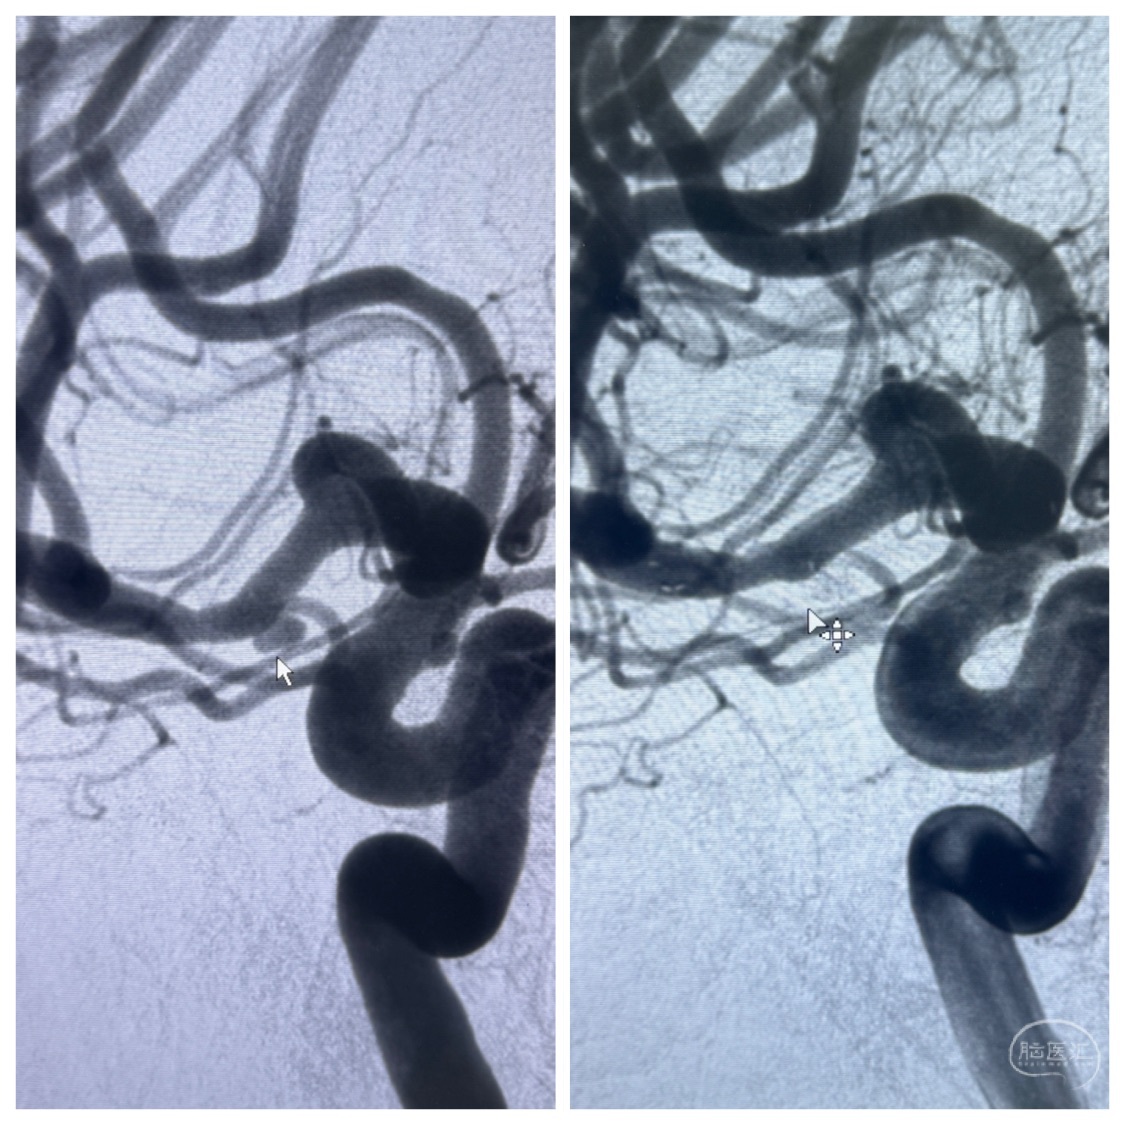

2023-11-24DSA:右侧大脑中动脉下干起始部动脉瘤,约2.3*2.5mm,形态规则

2023-12-04全麻下行支架辅助治疗

S-AB4-20mm

麻醉苏醒佳,遵嘱动作